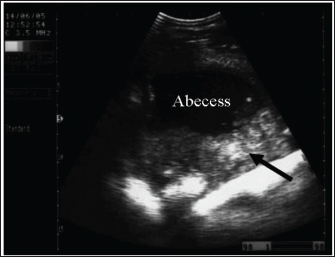

Spasmodic colic is usually characterized in horses by brief intermittent attacks of abdominal pain, pawing, rolling, and kicking the belly for a few minutes, then shaking and standing in a normal way for a few minutes until the next fit of pain reoccurs. Therefore, the affected animal presented with multiple skin wounds (Fig. 3). The horse suffering from spasmodic colic had increased peristaltic activity, which might be attributed to inflammatory conditions such as enteritis and colitis (Fikri et al., 2023). The ultrasonographic appearance of the abdominal organ showed that the cecum appeared with an echogenic wall, and the contents were of variable echogenicity. The wall thickness increased, and the peristaltic activity of the cecum was hypermotile on real-time ultrasonography. The left ventral colon appeared with increased wall thickness, and sacculations were detected in some cases, whereas, in others, it appeared with normal wall thickness. The descending colon has a thin echogenic wall and contains isoechoic ingesta that appear in continuous motion, indicating hypermotility of the bowel (Tharwat et al., 2008).

Intestinal ultrasonography generally shows increased intestinal peristalsis. The cecal wall appears echogenic, and the contents are of variable echogenicity. The wall thickness is increased, and the peristaltic activity of the cecum is detected as hypermotile on real-time ultrasonography (le Jeune and Whitcomb, 2014). The left ventral colon appears with increased wall thickness, and sacculations are detected in some cases, whereas, in others, it appears with normal wall thickness. The descending colon has a thin echogenic wall and contains isoechoic ingesta that appears in continuous motion (Fig. 4).

Fig. 4. Sonogram of 5 horses with spasmodic colic. Images A and B were taken at the right flank region and showed the echogenic cecal tissues with variable echogenicity and increased wall thickness. The peristaltic movement of the cecum was hypermotile during real-time scanning. Image C shows the spleen, descending colon, and left ventral colon obtained from the left 13th intercostal space. They appear normal, and only hyperperistalsis was detected. Image D shows the spleen and left ventral colon from the left 13 intercostal spaces. The spleen had a normal echotexture, the left ventral colon also had a normal echogenic wall, and only hypermotility of the left ventral colon was observed. Image E shows the spleen and descending colon. The spleen appears normal, and the descending colon appears as a circular echogenic wall with fluid and ingesta contents that appear with swirling motility more than expected.